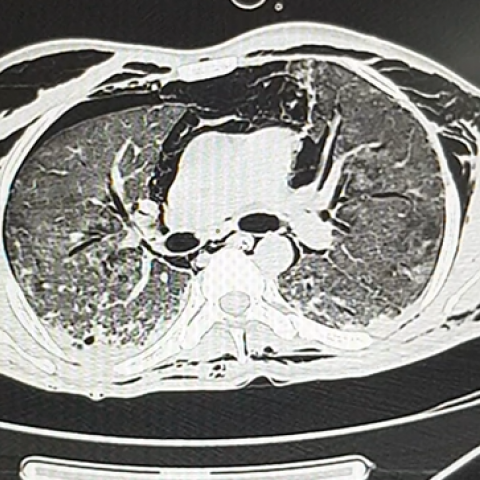

纵隔气肿ct图片

病例41纵膈气肿胸片ct

纵膈气肿ct